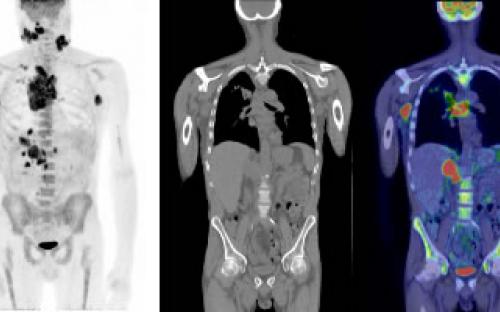

เทคโนโลยีถูกนำมาใช้ในแวดวงสุขภาพมากขึ้น HITAP มีส่วนร่วมวิจัยในประเด็นเกี่ยวกับ digital health มากขึ้น ไม่ว่าจะเป็นการใช้ปัญญาประดิษฐ์หรือ AI ในการสนับสนุนการทำงานของบุคลากรทางการแพทย์ ระบบการติดตามผู้ป่วยทางไกล (telemedicine) ไปจนถึงการประเมินภาพรวมและผลกระทบทั้งด้านความน่าเชื่อถือ ภาระงาน ประเด็นอ่อนไหวอย่างพรบ. ข้อมูลส่วนบุคคล (PDPA) เพื่อสร้างเป็นฐานความรู้สำหรับอนาคตของระบบสุขภาพไทยที่กำลังจะมุ่งไป